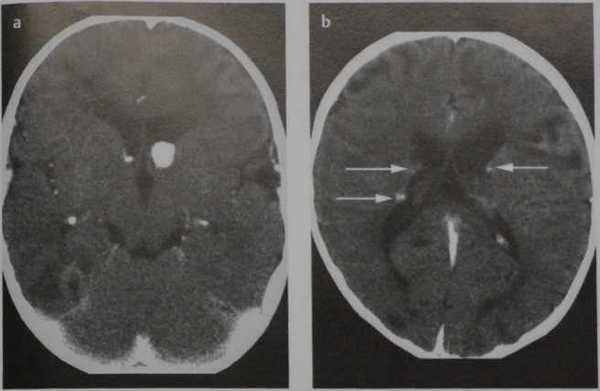

Туберозный склероз. КТ, аксиальный срез после введения КС. Кальцифицированная субэпендимальная опухоль в переднем роге левого бокового желудочка (гигантоклеточная астроцитома, а). Вдоль стенок бокового желудочка визуализируются множественные, накапливающие КС субэпендимальные узлы, некоторые из них кальцифицированные (гамартомы) (b; стрелки). Множественные, двусторонние, кортикальные и субкортикальные узлы в лобной, височной и затылочной долях (гамартия; а, b)

Туберозный склероз на изображениях визуализируются обызвествленные узлы или кальцифицированные субэпендимальные гамартомы.

2. КТ при туберозном склерозе:

• Бесконтрастная КТ:

о СЭУ:

- Вдолькаудоталамической вырезки > предсердия» височной

- 50% Са (прогрессирующее в течение одного года)

о Туберсы

- «Свежие»: гиподенсные/кортикальная Са++/субкортикаль-ное объемное образование

- «Старые»: изоденсные/Са++ (50% к 10 годам)

о Вентрикуломегалия встречается часто даже при отсутствии СЭГА

• КТ с контрастированием

о Контрастирование/увеличение размеров СЭУ - подозрение на СЭГА